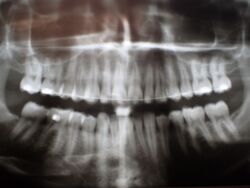

Es erfolgt dieErstuntersuchung und die Herstellung und Eingliederung eines adjustierten Aufbissbehelfs zum Nachweis einer CMD.